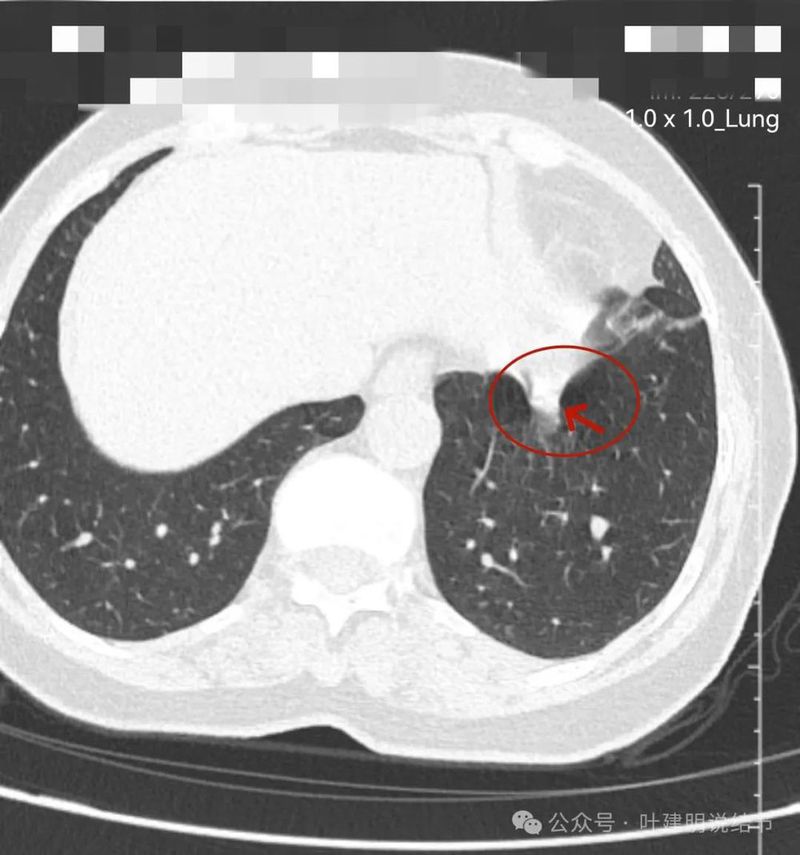

边比较为平直,密度仍实。

感觉两处不同的中心,如果连续层面看,应该是病灶不平的关系,与膈肌间仍有间隙,密度是实性的。

边缘区域的样子。

纵隔窗见病灶实性密度,与膈肌间有低密度线状间隙。

病灶密度稍不均。

较为边缘部分的纵隔窗样子。